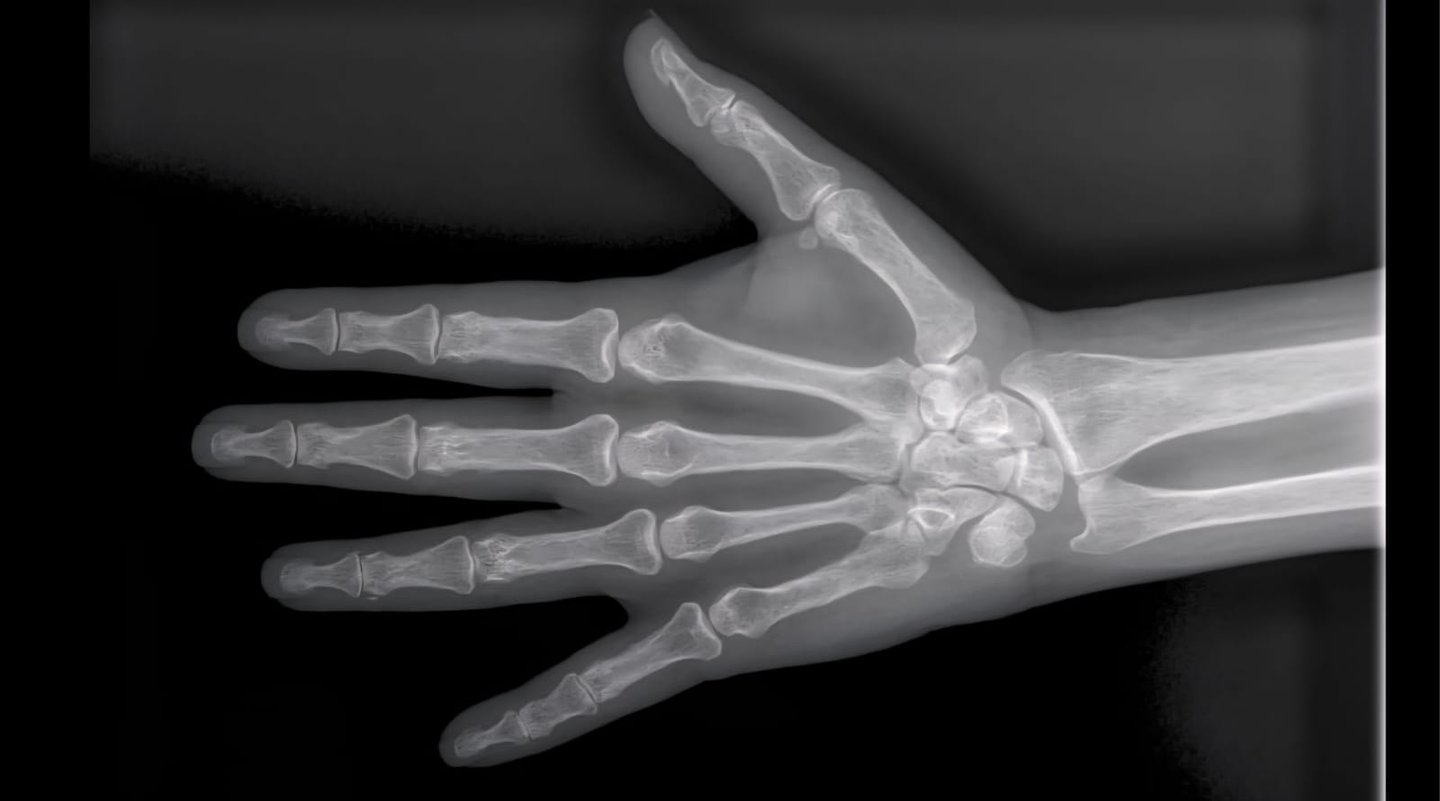

Hand X-rays

Detailed digital imaging for hand, wrist, and finger injuries or joint conditions. We provide high-resolution views for fracture diagnosis and orthopedic assessments with fast reporting.